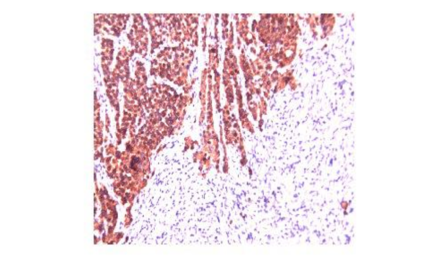

免疫组化:AE1/AE3(+);CK5/6(+);P40(+);CK7(-);Syn(-);CD56(-);Ki-67(+80%);P16(+);PD-L1(+,CPS:5);S100(-);HMB45(-),诊断结果为宫颈鳞癌II级。

7

图1. 免疫组化诊断为宫颈鳞癌II级

镜下所见:

14

图7. PD-L1检测结果显示阳性

结果判读:

PD-L1表达阳性,CPS≥1(CPS=15)。